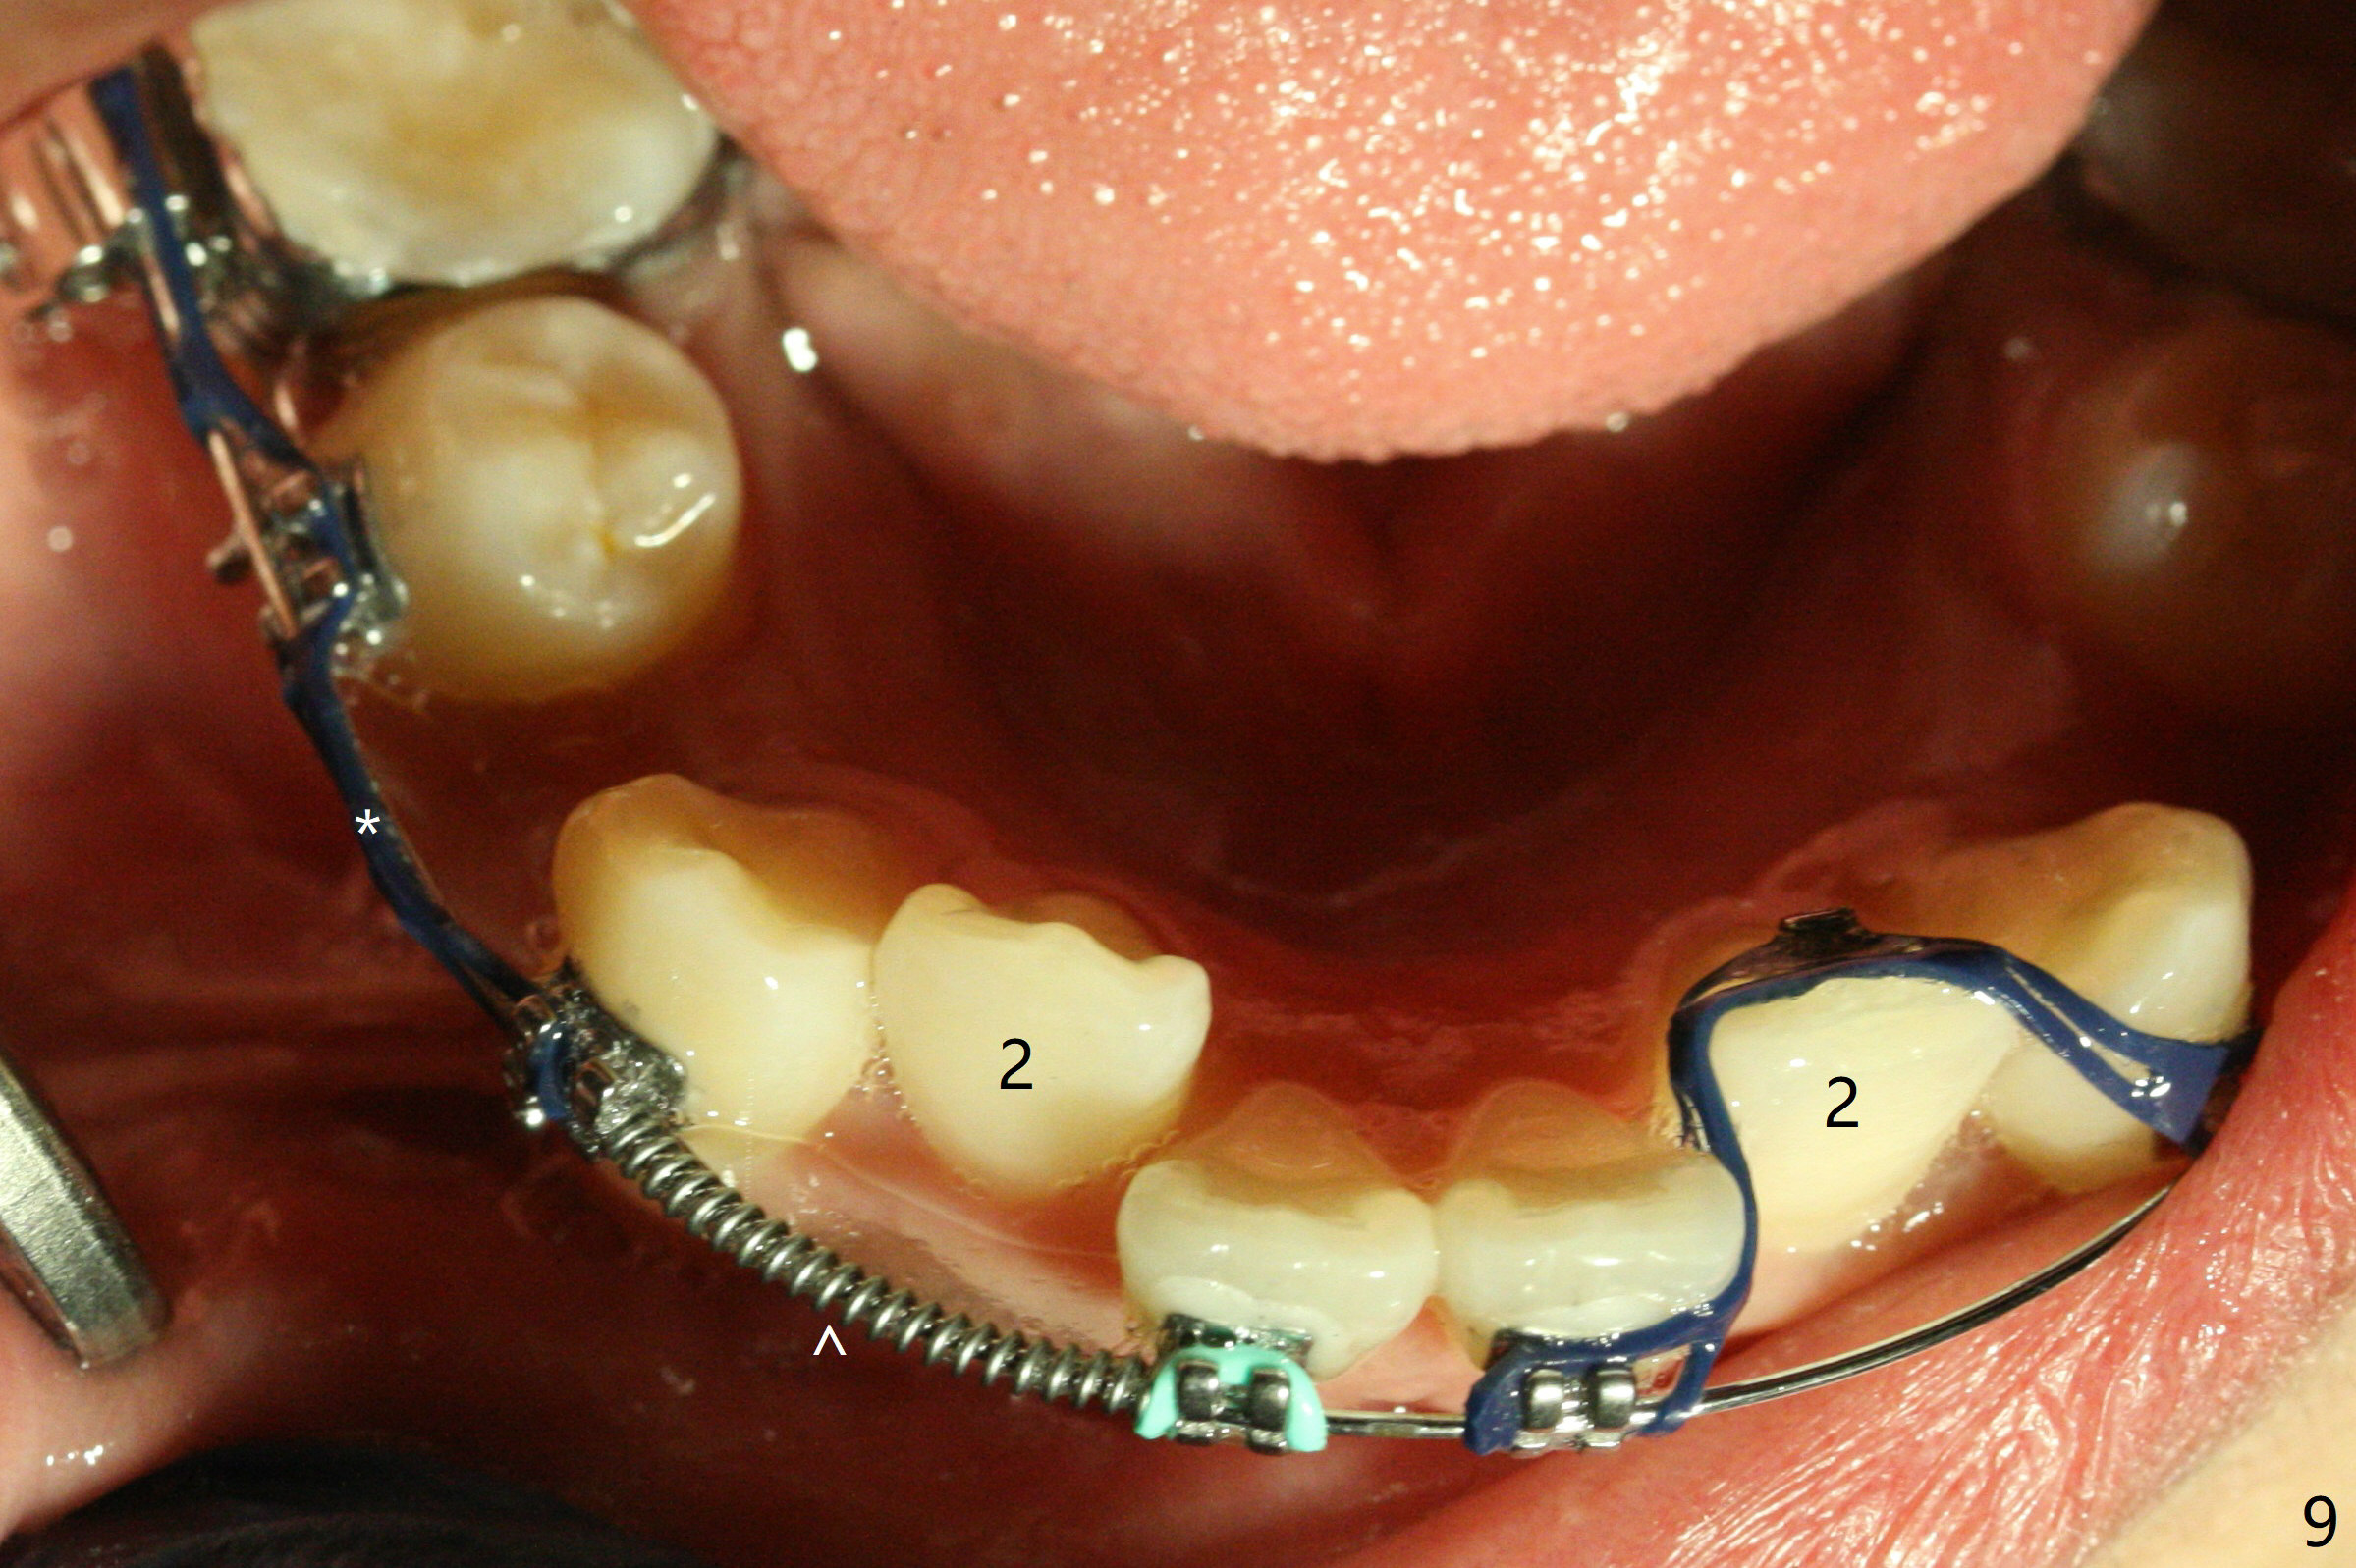

Three months post banding, the cross bite at 7s is corrected; with 7s' supraeruption and 6s' infraocclusion (because of occlusal composite (just removed), Fig.7,8), anterior open bite occur. Next visit place brackets in L7s with flexible wire. While 2 mechanisms are applied to gain more space for LR2 (Fig.9 *, ^), a special mechanism is utilized to correct LL2 cross bite (space gained). If the space for UR2 (Fig.10) is insufficient next appointment, what should we do? Otherwise, what should be done?